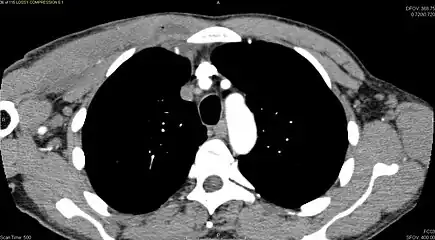

CT with IV contrast showing enlargement and heterogeneous hypodensity in the right pectoralis major muscle. A focal abscess collection with gas within it is present medially. There are enlarged axillary lymph nodes and some extension into the right hemithorax. Note the soft tissue and phlegmon surrounding the right internal mammary artery and vein. The patient was HIV+ and the pyomyositis is believed to be due to direct inoculation of the muscle related to parenteral drug abuse. The patient admitted to being a "pocket shooter" -